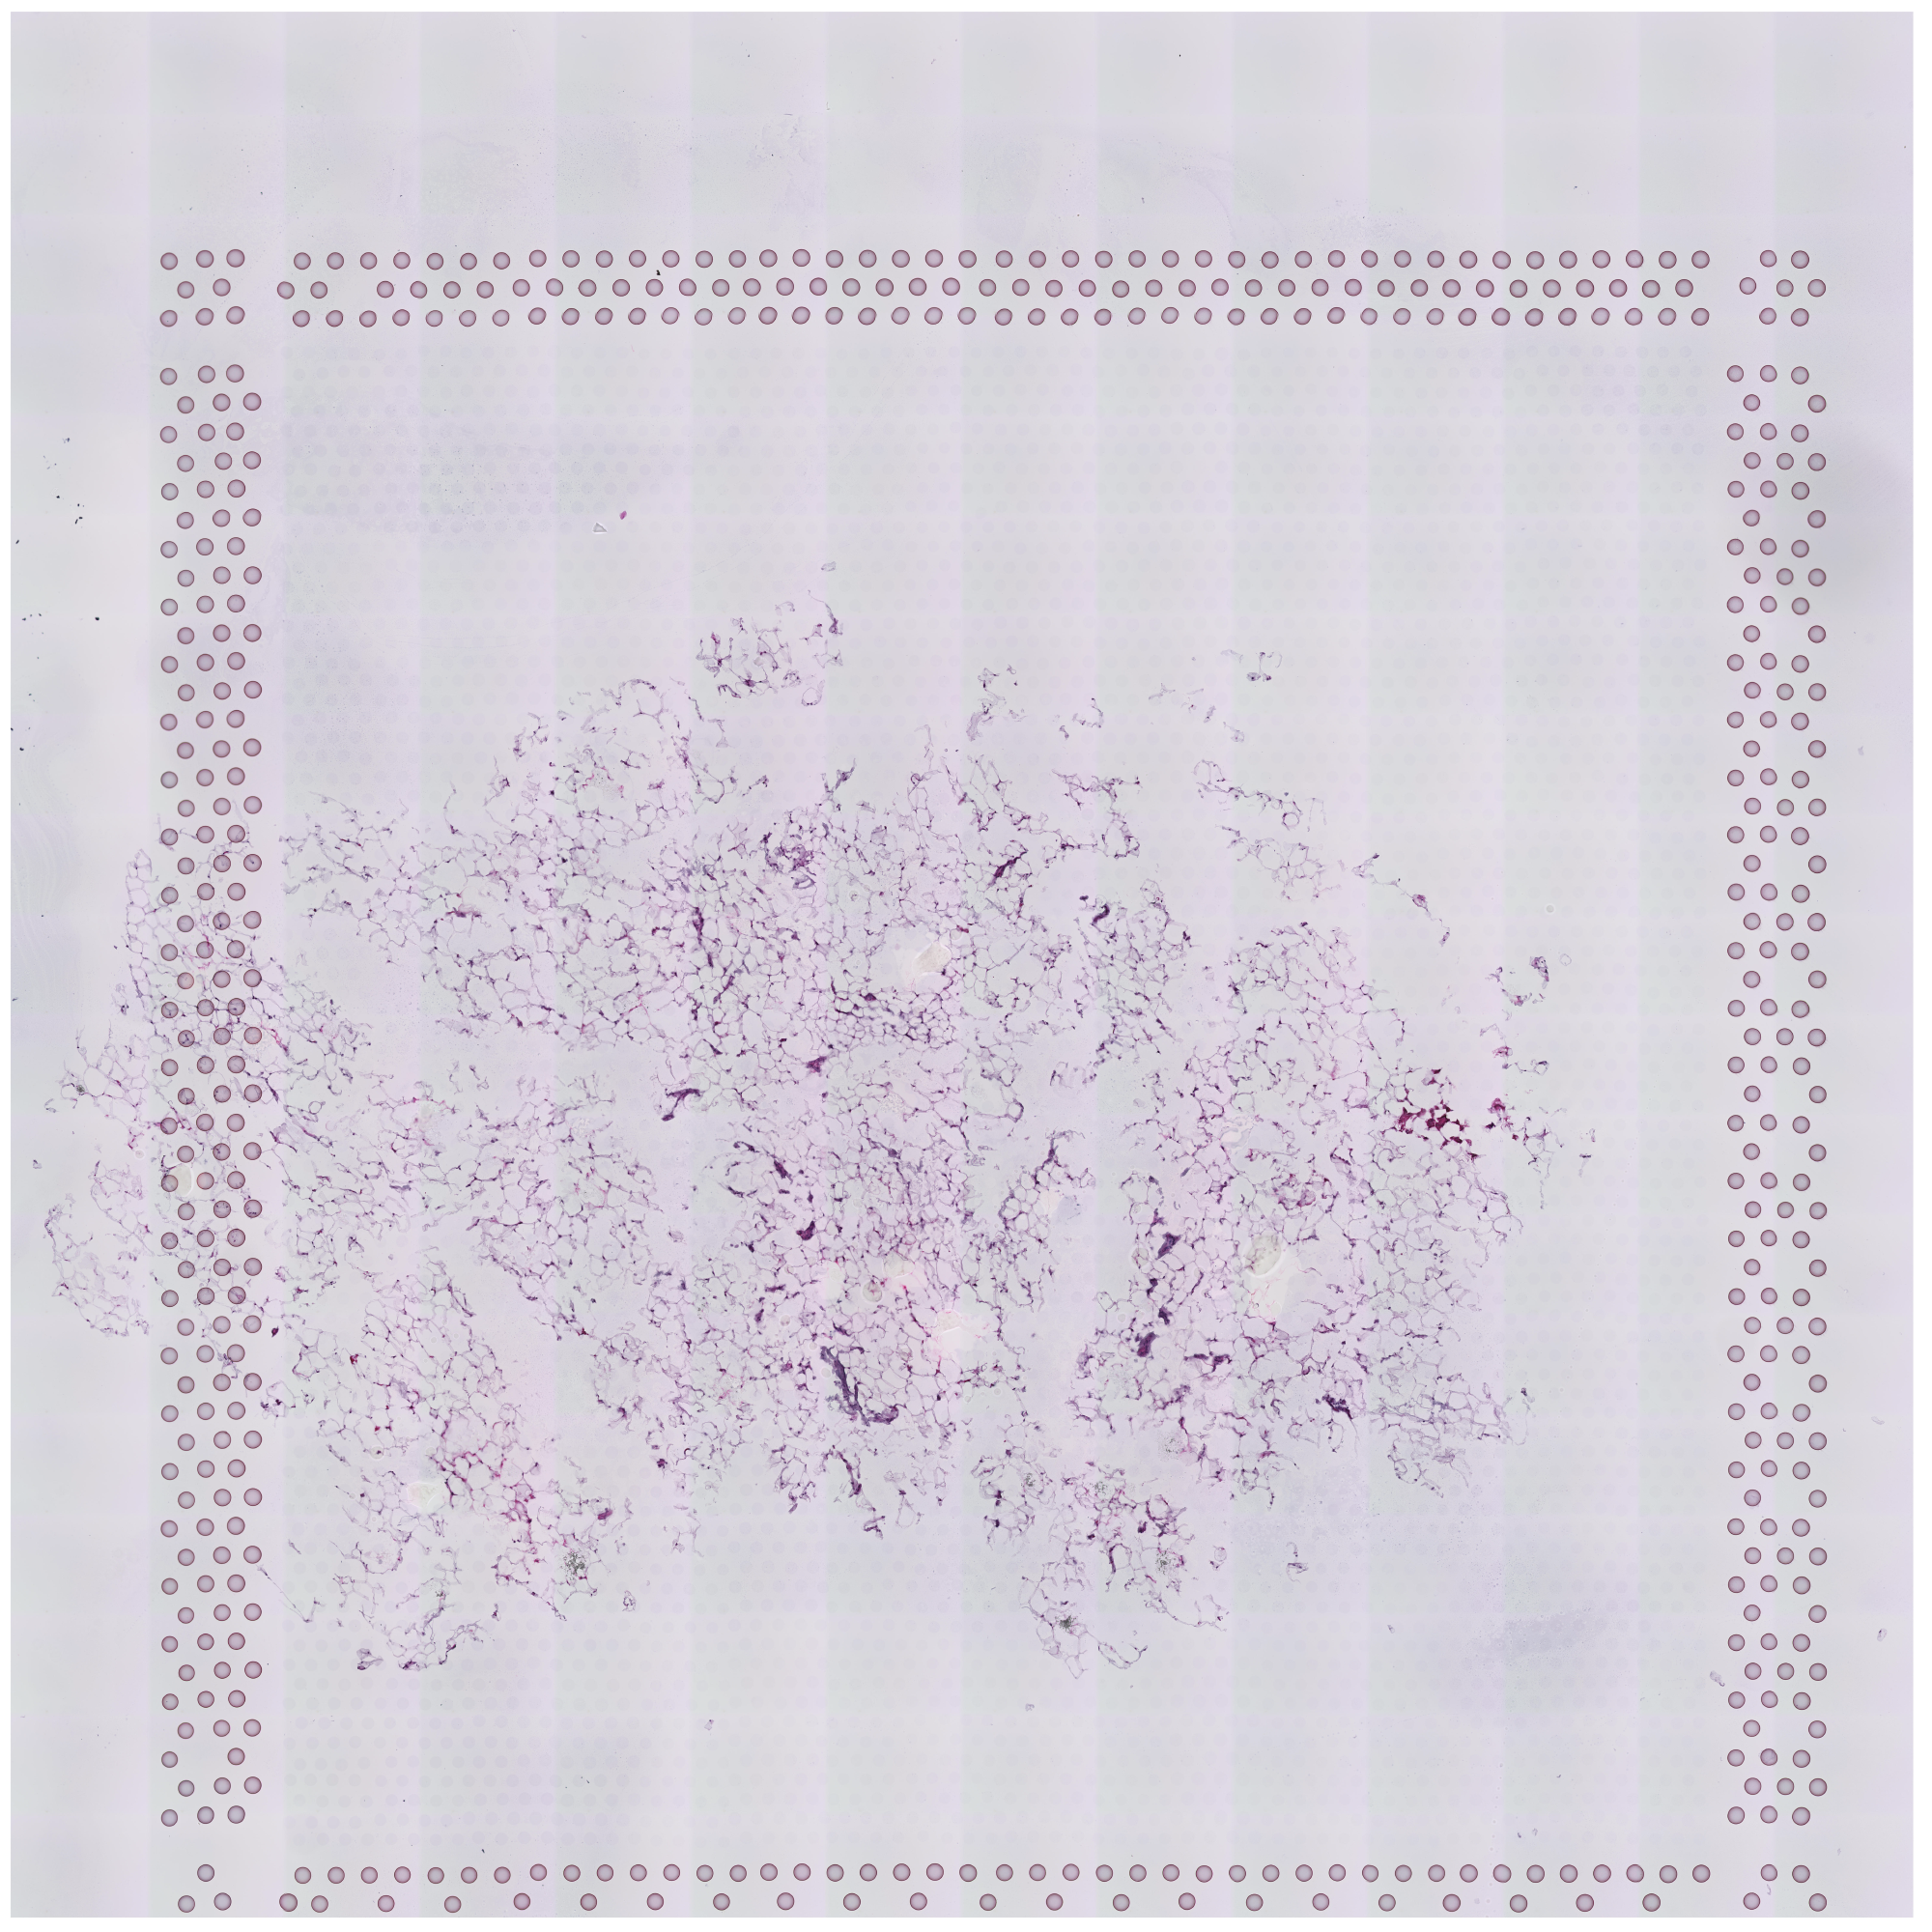

tissue_hires_image.png